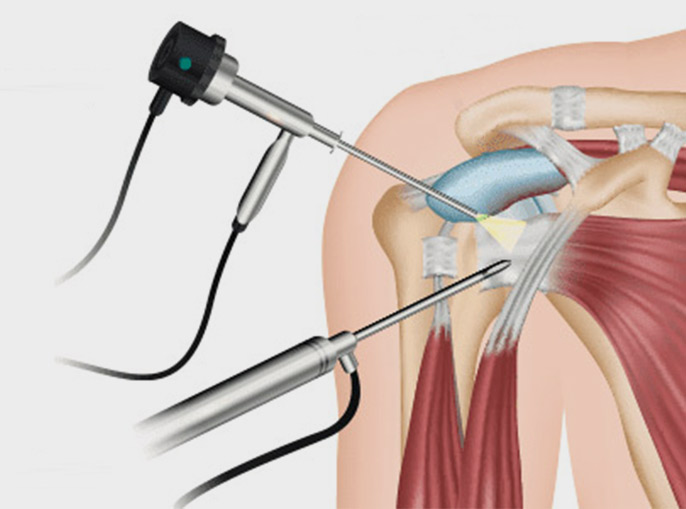

Arthroscopy is a groundbreaking procedure that entails the insertion of a specialized camera, known as an arthroscope, into the joint. This technique is invaluable in allowing surgeons to gain an inside view of the joint, facilitating diagnosis and treatment of joint issues.

Frozen shoulder or adhesive capsulitis condition (resulting from inflammation and stiffening of connective tissue surrounding glenohumeral joint) can be corrected successfully by using minimally invasive arthroscopic surgery.

A Bankart Lesion is a shoulder injury where the labrum, a cartilage ring, separates from its bony attachment at the glenoid rim. The key to treating this condition effectively is arthroscopic surgery.In this procedure, arthroscopic surgery is used to delicately reattach the torn labral tissue to the rim of the shoulder socket (glenoid). This precise approach offers an effective solution for Bankart Lesion, helping patients regain shoulder stability and function.